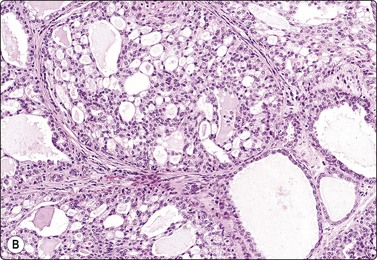

Phyllodes tumor (Figs 7.29-7.32)117-123

Phyllodes tumor (PT) is a biphasic epithelial/stromal neoplasm of the breast. In contrast to fibroadenoma, PT is a rare tumor comprising less than 0.3% of all breast tumors. It is classified as benign, low grade (borderline) and high grade (malignant) based on histologic features. Stromal cellularity and overgrowth, atypia, mitotic activity, and invasive growth pattern at tumor periphery define whether a PT is benign, low grade or high grade. Benign PTs do not metastasize, but may locally recur if incompletely excised. High-grade PTs behave like sarcomas with higher potential for recurrence and metastasis. Low-grade PTs fall in between.

image image

Fig. 7.29 Benign phyllodes tumor

(A) Huge, slowly growing breast mass in a 40-year-old woman; (B) FNB smears were cellular, dominated by dispersed cells with bare oval or plump spindle nuclei (MGG, HP).

Fig. 7.30 Borderline phyllodes tumor

Smears dominated by mildly atypical, both plump and slender spindle cells, single and in loose tissue fragments with fibrous stroma; a few sheets of bland duct epithelium (A, MGG; B, Pap, HP).

Fig. 7.31 Malignant phyllodes tumor

(A) Mainly dispersed spindle cells showing moderate nuclear atypia, no epithelial cells. Invasive growth demonstrated in tissue sections; multiple recurrences (MGG, IP); (B) Another case showing numerous spindle cells with more marked atypia and a sheet of bland epithelium (Pap, HP).

image

Fig. 7.32 Fibroadenoma mimicking benign phyllodes tumor on core needle biopsy (H&E, IP).

Aspiration biopsy can accurately diagnose malignant PTs in most cases. On the benign/borderline end of the spectrum, cytologic features of fibroadenoma and PT overlap, making FNA diagnosis difficult (see Fig. 7.23). Precise preoperative distinction is important for optimal patient management. Classic cytologic features in PT are similar to fibroadenoma. However, as opposed to fibroadenoma, stromal fragments are larger, increased in number (stromal overgrowth) and are hypercellular (phyllodes fragments); the single stromal cells in the background are plumper than the typical oval bare nuclei seen in fibroadenoma. These single cells are intact spindled cells with retained cytoplasm (not naked nuclei), and variable degrees of nuclear atypia with nucleoli and pleomorphism. However, some of these features may be entirely lacking in benign and low-grade PTs even after retrospective review of smears, making their differentiation from fibroadenoma virtually impossible. It is not surprising that a considerable portion of benign and low-grade PTs are initially diagnosed as fibroadenoma on cytology.117,120,121 This in part reflects sampling problems as hypo- and hypercellular areas tend to alternate within PTs. Another important diagnostic pitfall in PTs is the presence of significant epithelial proliferation including atypical ductal epithelial hyperplasia. If these areas are sampled by aspiration biopsy, this may lead to a false diagnosis of epithelial neoplasm. In our experience, we encountered this problem even with high-grade (malignant) PTs; one such retroareaolar case required core biopsy due to inability of aspiration biopsy to rule out an atypical papillary lesion. In addition, focal malignant transformation may be missed by FNA sampling.

Page 174

The diagnosis of PT on CNB is equally as challenging (Fig. 7.32). It is especially difficult to differentiate cellular fibroadenoma from benign/low-grade PT. In comparison, in one study, the possibility of PT was raised in 23% on FNB and 65% on core biopsy.122 In two others, 11 of 44 (25%), and 9 of 23 (39%) of surgically resected PTs were reported as fibroadenoma or benign on core biopsy.123,124 Similar to FNB, some PTs are diagnosed as fibroadenoma on core biopsy because of tumor heterogeneity. Marked nuclear pleomorphism and mitotic activity suggest frankly malignant phyllodes tumor (Fig. 7.31A,B).